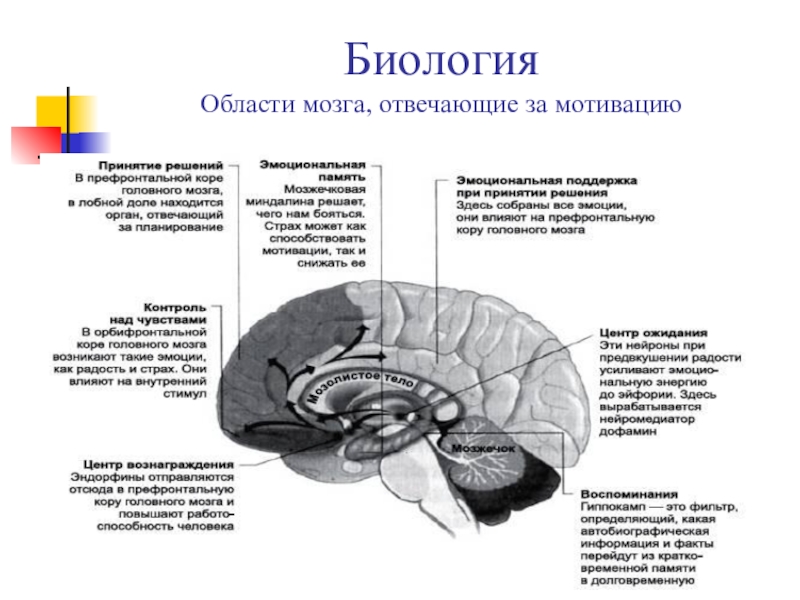

Раздел: Моменты озарения